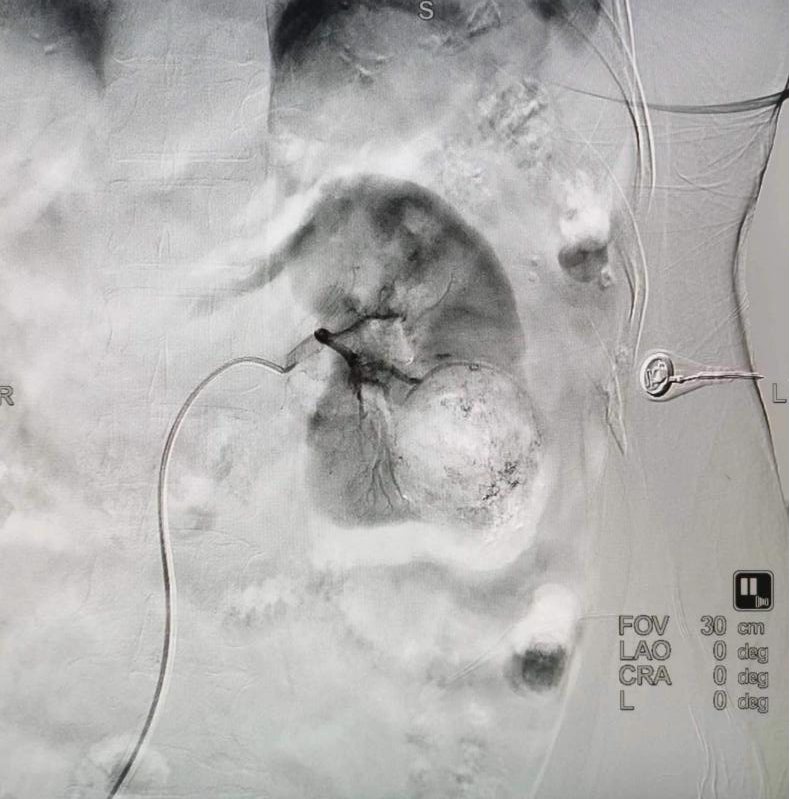

患者错构瘤造影

朱晖教授告诉刘女士,目前瘤体较大,压迫周围正常组织,一旦肿瘤破裂,容易大出血造成休克,威胁生命安全,因此,建议尽早进行手术治疗。

7月25日,朱晖教授与放射科主任罗谞成为患者成功施行了介入肾动脉造影+超选择性肾动脉载瘤动脉分支栓塞术,手术仅用时一小时。术后,刘女士肾脏错构瘤栓塞完全,无正常肾组织损伤,无相关并发症。